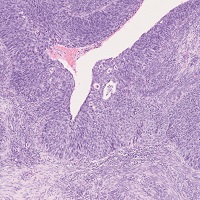

【子宮頚部/悪性腫瘍】

扁平上皮癌